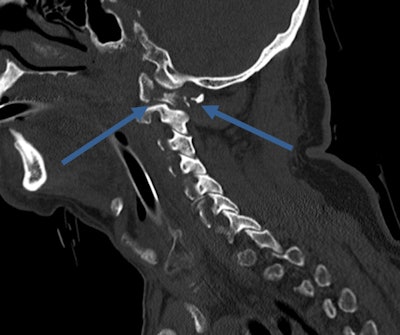

However, very early stages of bleeding, especially in the brain, may be hard to detect, he cautions. Radiologists should be aware of possible hyperacute intracranial bleeding without tremendous density above the surrounding parenchyma.

"If in doubt, repeat the scan. In most cases when a second scan seems appropriate, limiting the procedure to particular organs is sufficient," he said.